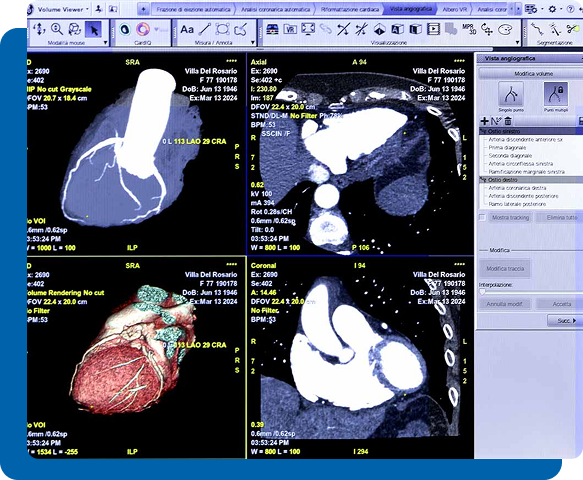

La TAC Coronarica è un esame diagnostico non invasivo che consente di visualizzare in modo dettagliato le arterie coronarie e valutare la presenza di eventuali restringimenti o placche aterosclerotiche.

La TAC Coronarica è una Tomografia Assiale Computerizzata ad alta definizione che utilizza mezzo di contrasto per studiare in modo preciso il decorso e lo stato delle arterie coronarie. Grazie alla rapidità di acquisizione e alla qualità delle immagini, consente di analizzare il cuore e i vasi coronarici in pochi secondi, riducendo il disagio per il paziente.